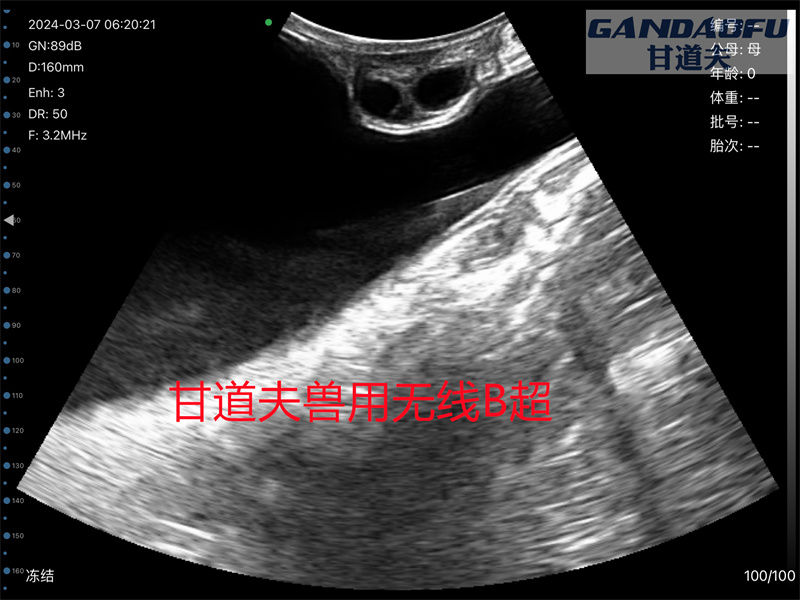

甘道夫馬用B超驢用B超免費(fèi)提供馬用B超使用方法,驢用B超測(cè)孕儀實(shí)踐教學(xué),獸用B超使用方法包教包會(huì),使用高清無(wú)線馬智能B超測(cè)孕和測(cè)牛驢一樣都是在直腸內(nèi)檢測(cè),如圖所示,驢馬配種后15-20天即可快速檢測(cè)出來(lái)驢馬懷孕狀態(tài)準(zhǔn)確率高,操作方便,簡(jiǎn)單易學(xué)歡迎大家前來(lái)交流學(xué)習(xí)。

使用甘道夫無(wú)線馬用智能B超獸用B超GDF-W9可以快速檢母馬發(fā)情狀態(tài)卵泡發(fā)育趨勢(shì),選擇理想的時(shí)間為母馬進(jìn)行配種可以快速提升母馬繁殖育種的速度,母馬屬于是季節(jié)性多次發(fā)情動(dòng)物,在繁育季節(jié)(春夏3-8月),非懷孕母馬出現(xiàn)一個(gè)接一個(gè)的發(fā)情周期,母馬發(fā)情周期的定義:從一次發(fā)情開(kāi)始至下次發(fā)情開(kāi)始所需要的時(shí)間(平均約21天)。由于種公馬體質(zhì)和配種能力強(qiáng)弱不同,每匹公馬所配的母馬數(shù)相差很大,一般公、母馬比例為1∶20~25,每匹公馬與相應(yīng)數(shù)量的母馬組成一個(gè)小群,數(shù)個(gè)小群形成一個(gè)大群。公馬20月齡左右成熟,4歲開(kāi)始配種,6~10歲配種能力強(qiáng),一般利用年限12~15年。母馬16月齡左右成熟,3歲開(kāi)始配種,一般利用年限15~20年;發(fā)情季節(jié)為4~7月份,發(fā)情周期23天,發(fā)情持續(xù)期4~7天,妊娠期337天左右;年平均受胎率90.0%,年產(chǎn)駒率50%~85%。幼駒初生重公駒(42.53±6.79)kg,母駒(38.00±6.24)kg;幼駒斷奶重公駒(108.53±6.43)kg,母駒(104.0±5.27)kg。 馬用B超測(cè)繁殖母馬發(fā)情懷孕方法步驟

1、使用甘道夫無(wú)線馬用智能B超可以在母馬孕前孕中孕后實(shí)時(shí)檢測(cè),快速掌握母馬發(fā)情狀態(tài)卵泡發(fā)育大小,母馬的發(fā)情時(shí)間是配種成功的關(guān)鍵。如果母馬沒(méi)有發(fā)情或發(fā)情時(shí)間不合適,可能導(dǎo)致配種失敗。因此,在選擇公馬進(jìn)行配種時(shí),需要考慮母馬的發(fā)情時(shí)間和健康情況,確保配種的成功。在配種前,我們還需要注意母馬的健康狀況。母馬需要在配種前接受身體檢查,確保她們身體健康,并且能夠正常懷孕和分娩。如果母馬存在健康問(wèn)題,需要事先進(jìn)行治療并得到獸醫(yī)的指導(dǎo)。